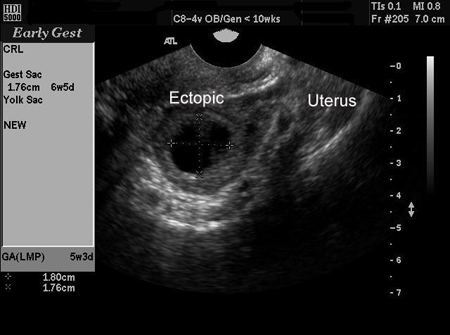

An ectopic pregnancy can be definitively diagnosed via ultrasound when a gestational sac with a yolk sac, or embryo, or both, is noted in the adnexa.[47] Not all ectopic pregnancies can be visualised on ultrasound; however, with increasingly high-resolution ultrasound and expert sonography, studies have shown that TVUS is both highly sensitive and specific in the diagnosis of ectopic pregnancy. However, there remains a significant proportion of cases (between 5% and 42%) where neither an intrauterine nor an ectopic pregnancy can be visualised on ultrasound. In these cases, the descriptive term pregnancy of unknown location (PUL) is used.[48][49][Figure caption and citation for the preceding image starts]: Ultrasound image of ectopic pregnancyFrom the collection of Dr Melissa Fries; used with permission [Citation ends].

[Figure caption and citation for the preceding image starts]: Ultrasound image of ectopic pregnancyFrom the collection of Dr Melissa Fries; used with permission [Citation ends].